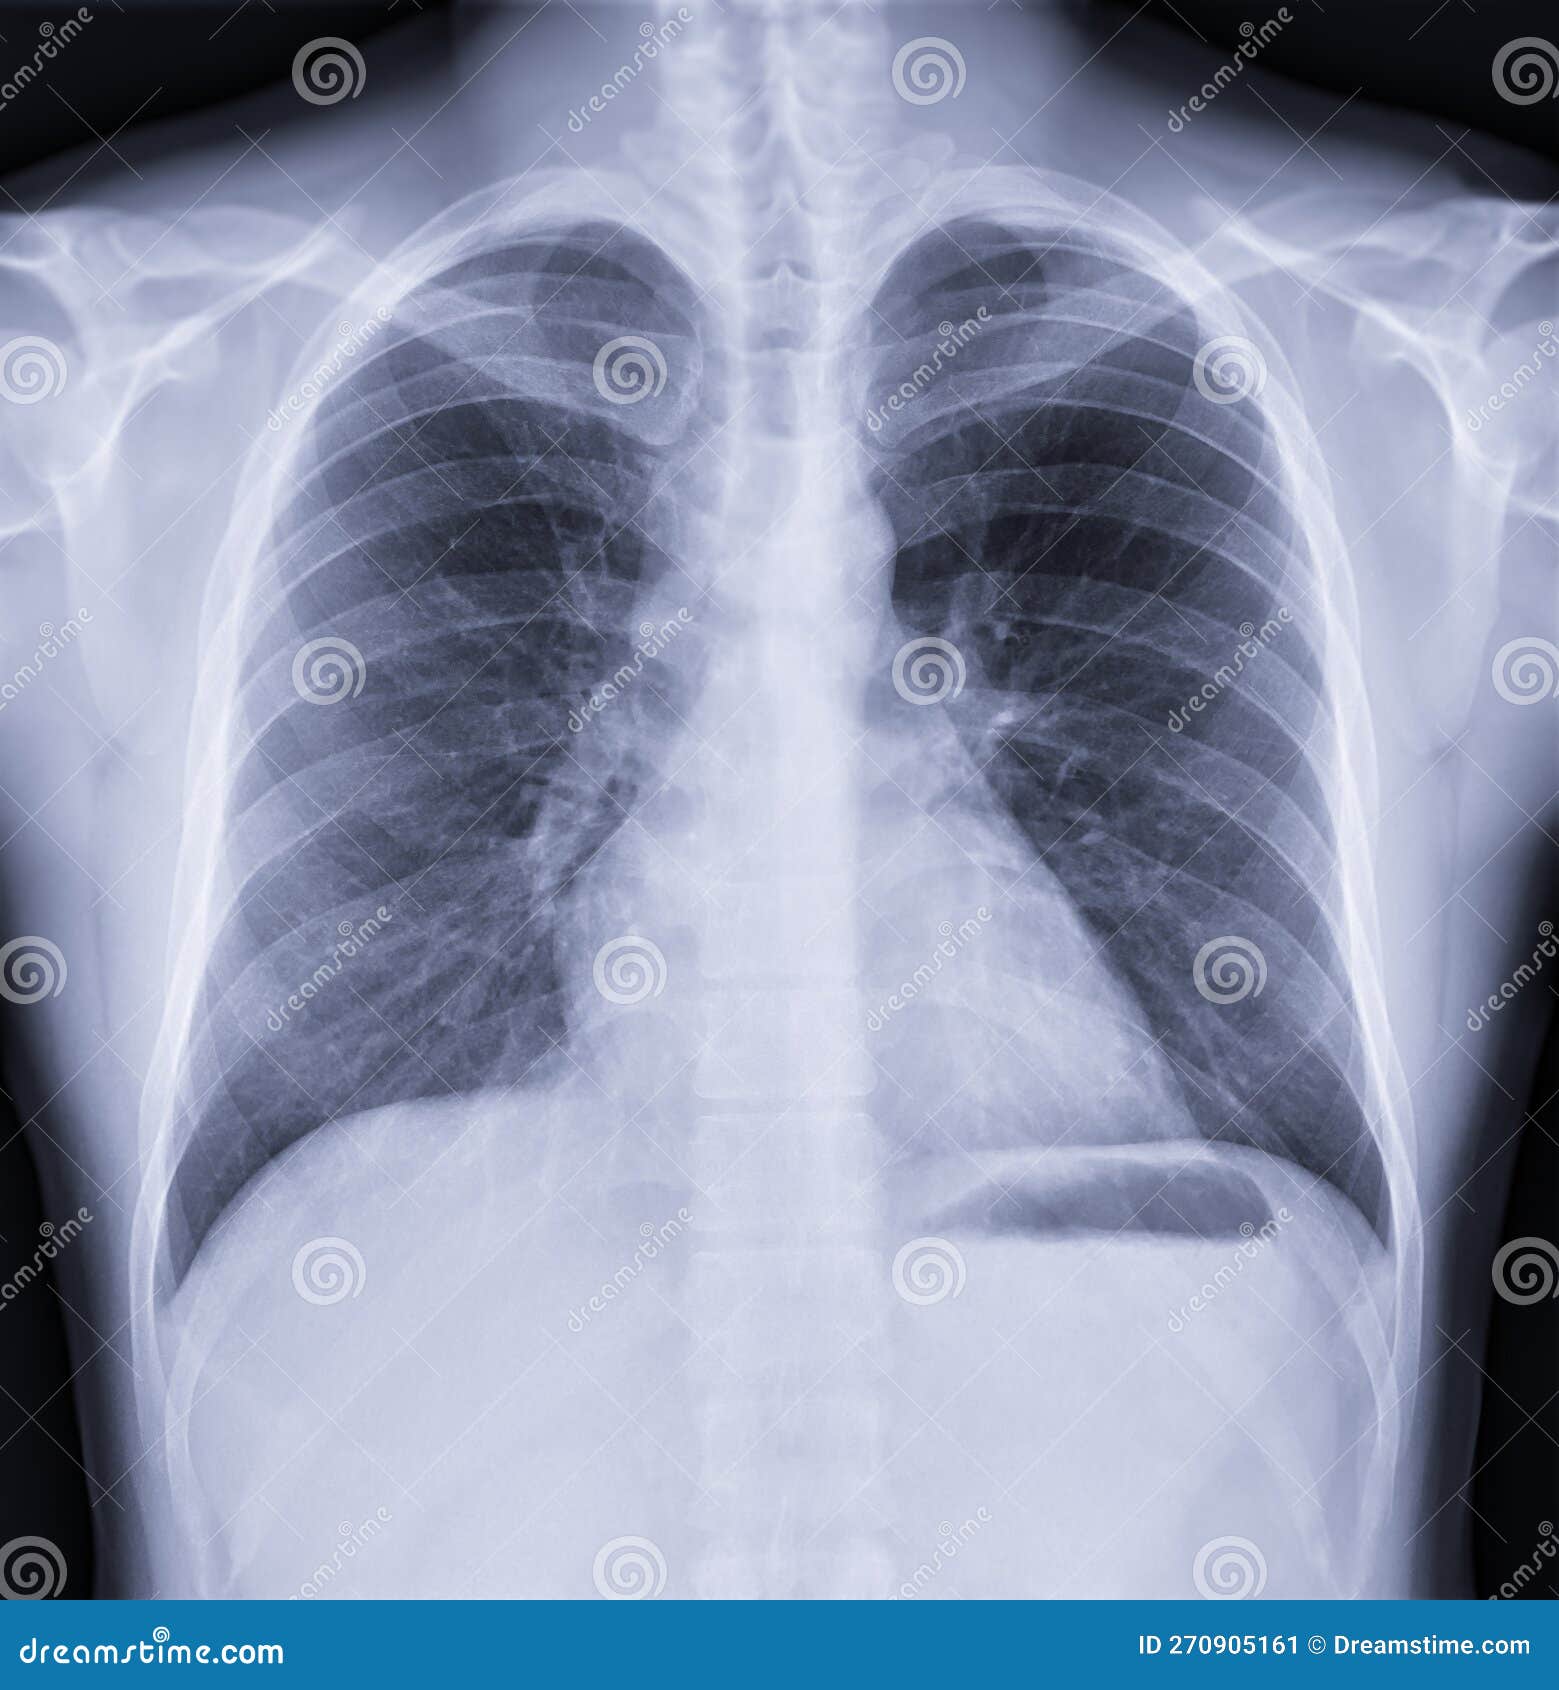

Chest X-ray Stock Photo. Image Of Radiography, Radiology - 9196496

www.dreamstime.comchest ray preview

www.dreamstime.comchest ray preview

www.colourbox.comNormal Chest X-Ray - Black And White Radiograph Stock Photo - Image Of

www.colourbox.comNormal Chest X-Ray - Black And White Radiograph Stock Photo - Image Of

Chest X-ray Image , Normal Chest Stock Image - Image Of Hospital